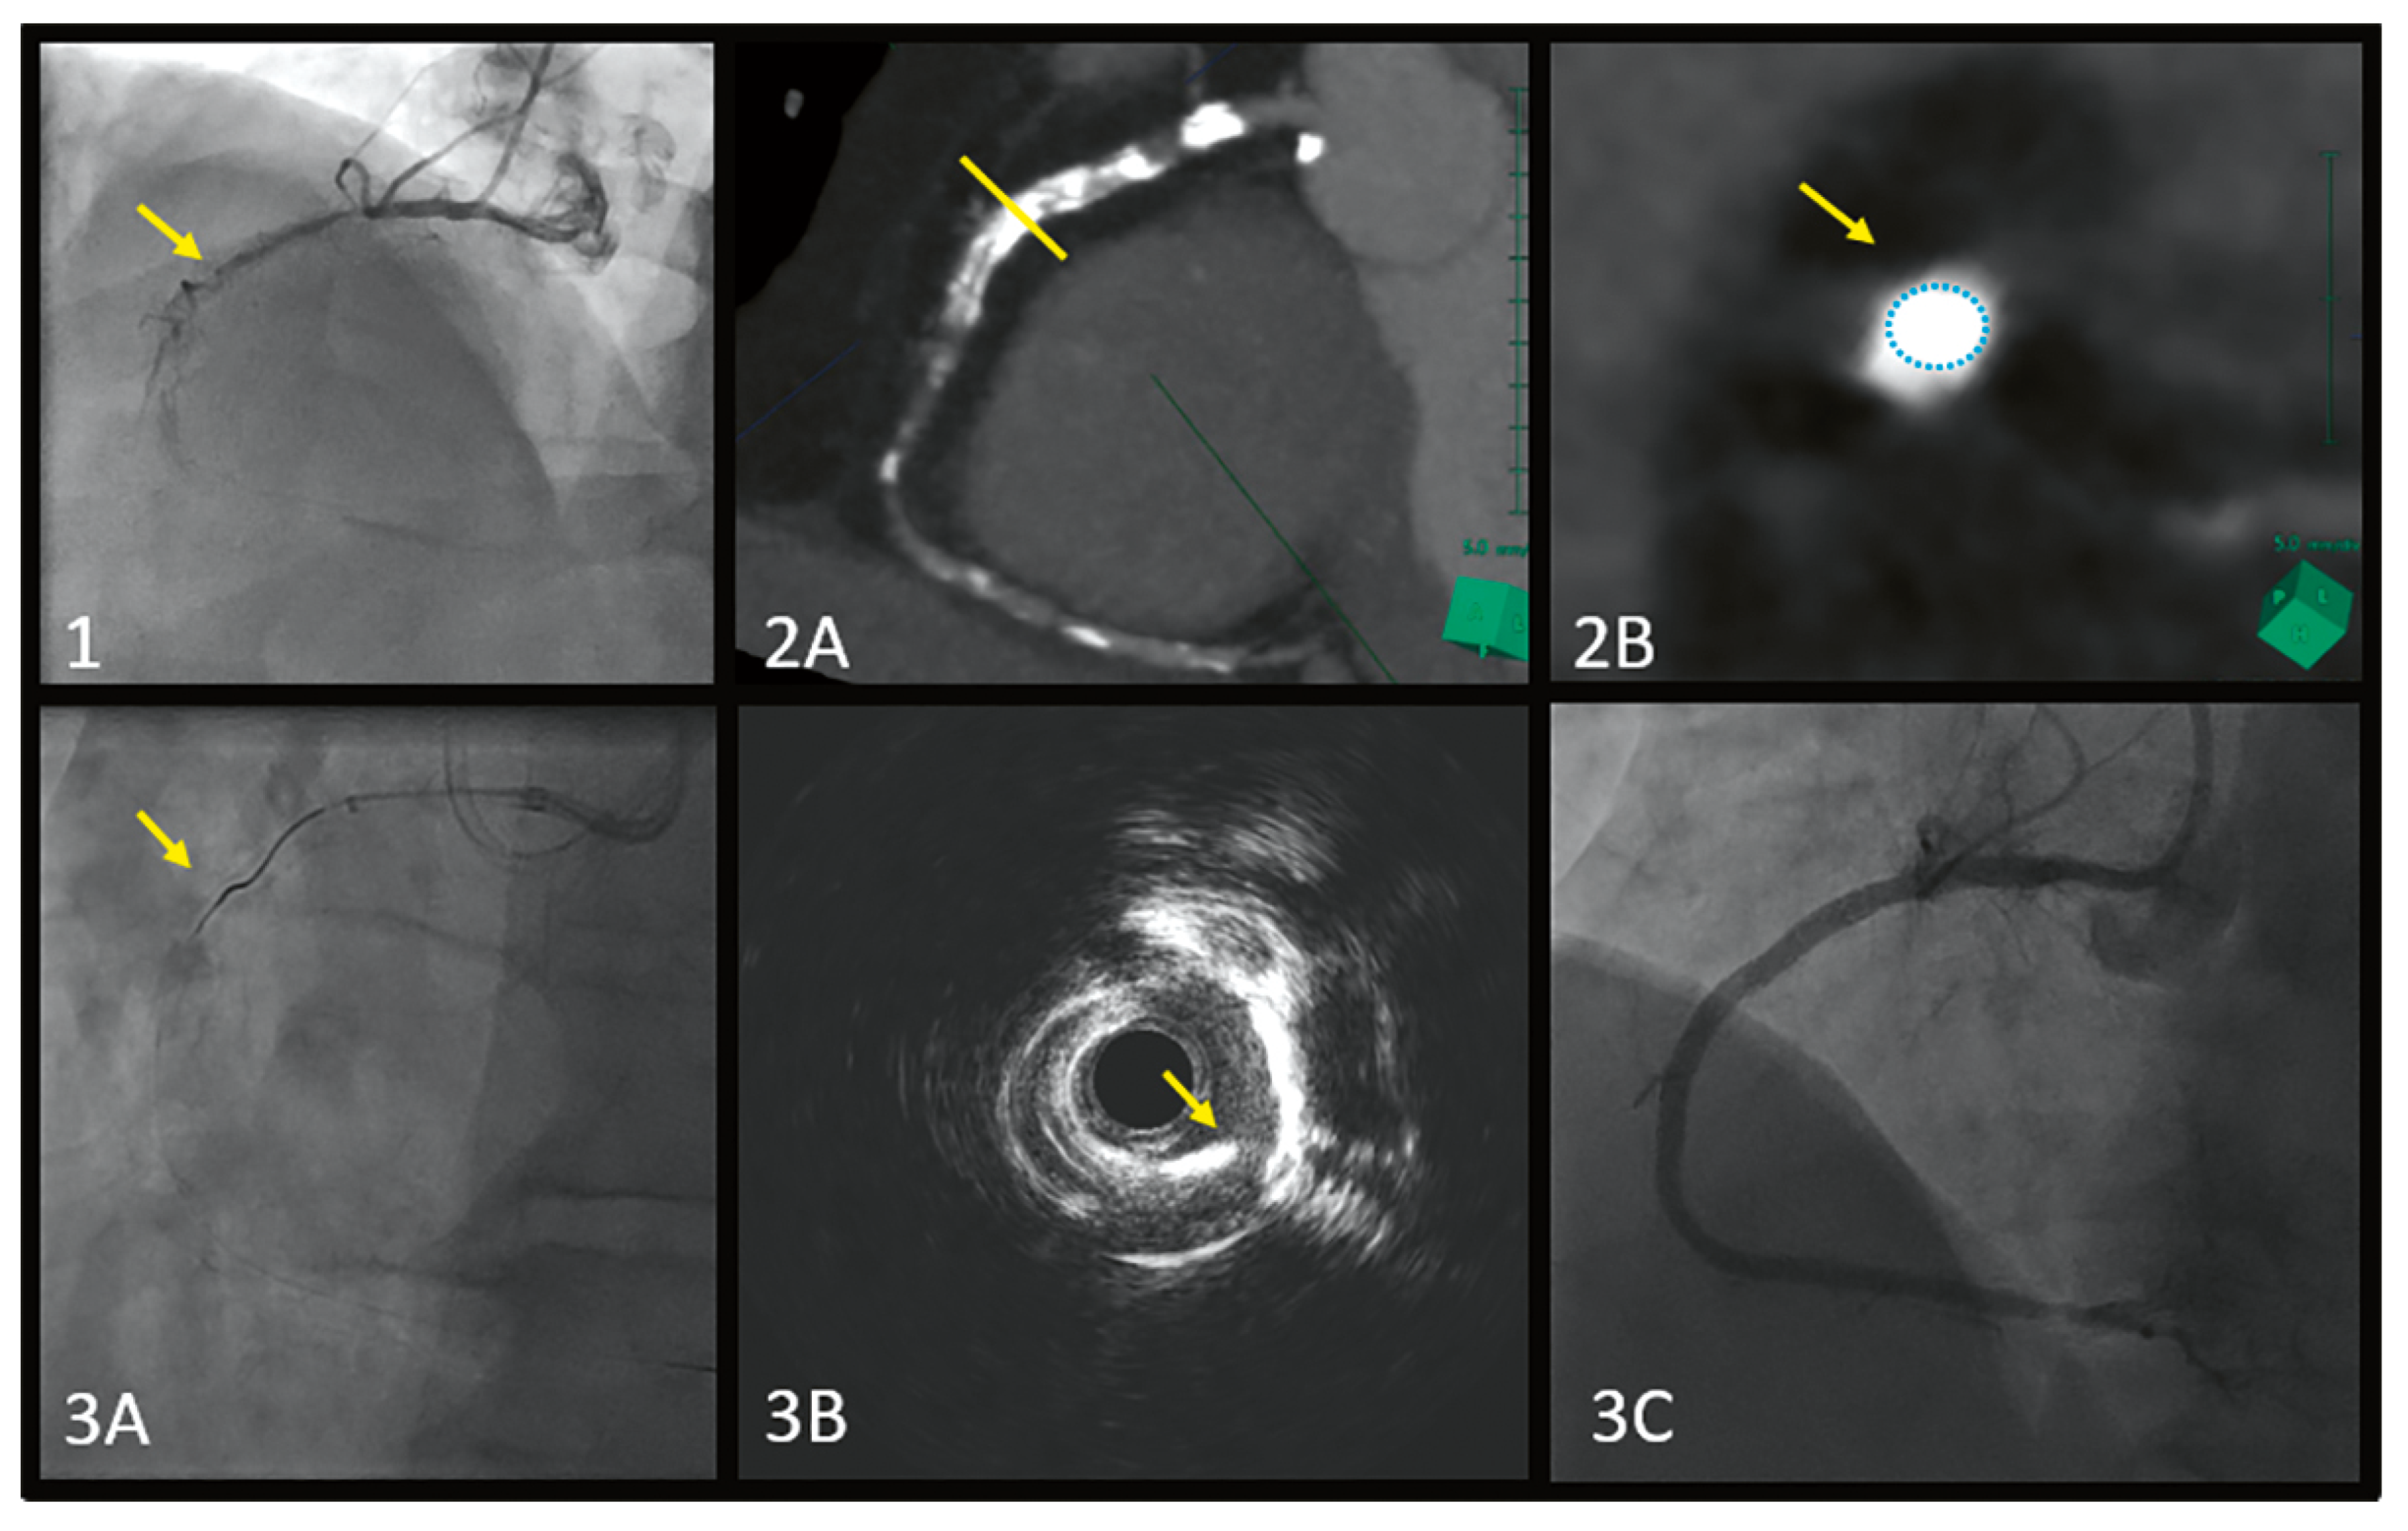

Full Moon Coronary Calcium Seen on Cardiac Tomography, Can It Change PCI Decision-Making and Procedure?